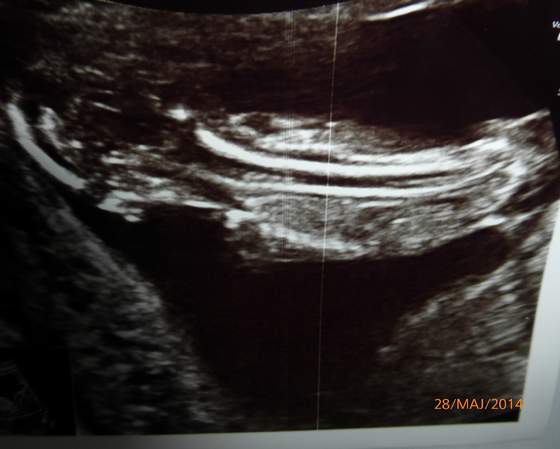

P1030176.jpg oto moje dziecię od tyłu :-)

Prawie 6,5 cm szczęścia:-D, cudownie.